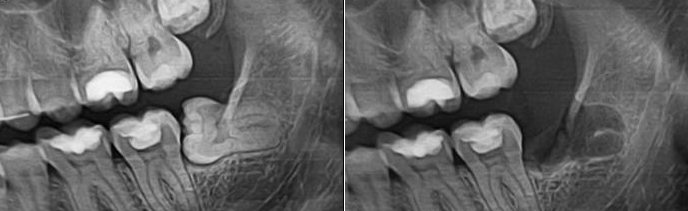

Удаление верхнего зуба мудрости: фото до и после

К ретинированным (непрорезавшимся) восьмеркам применяется иной подход. Чтобы извлечь их из десны, приходится делать разрез. Перед операцией стоматолог анализирует рентгенограмму: важно определить границы пазухи носа по отношению к корням верхнего зуба мудрости: чем ближе она располагается, тем больше риск ее перфорации или прободения.